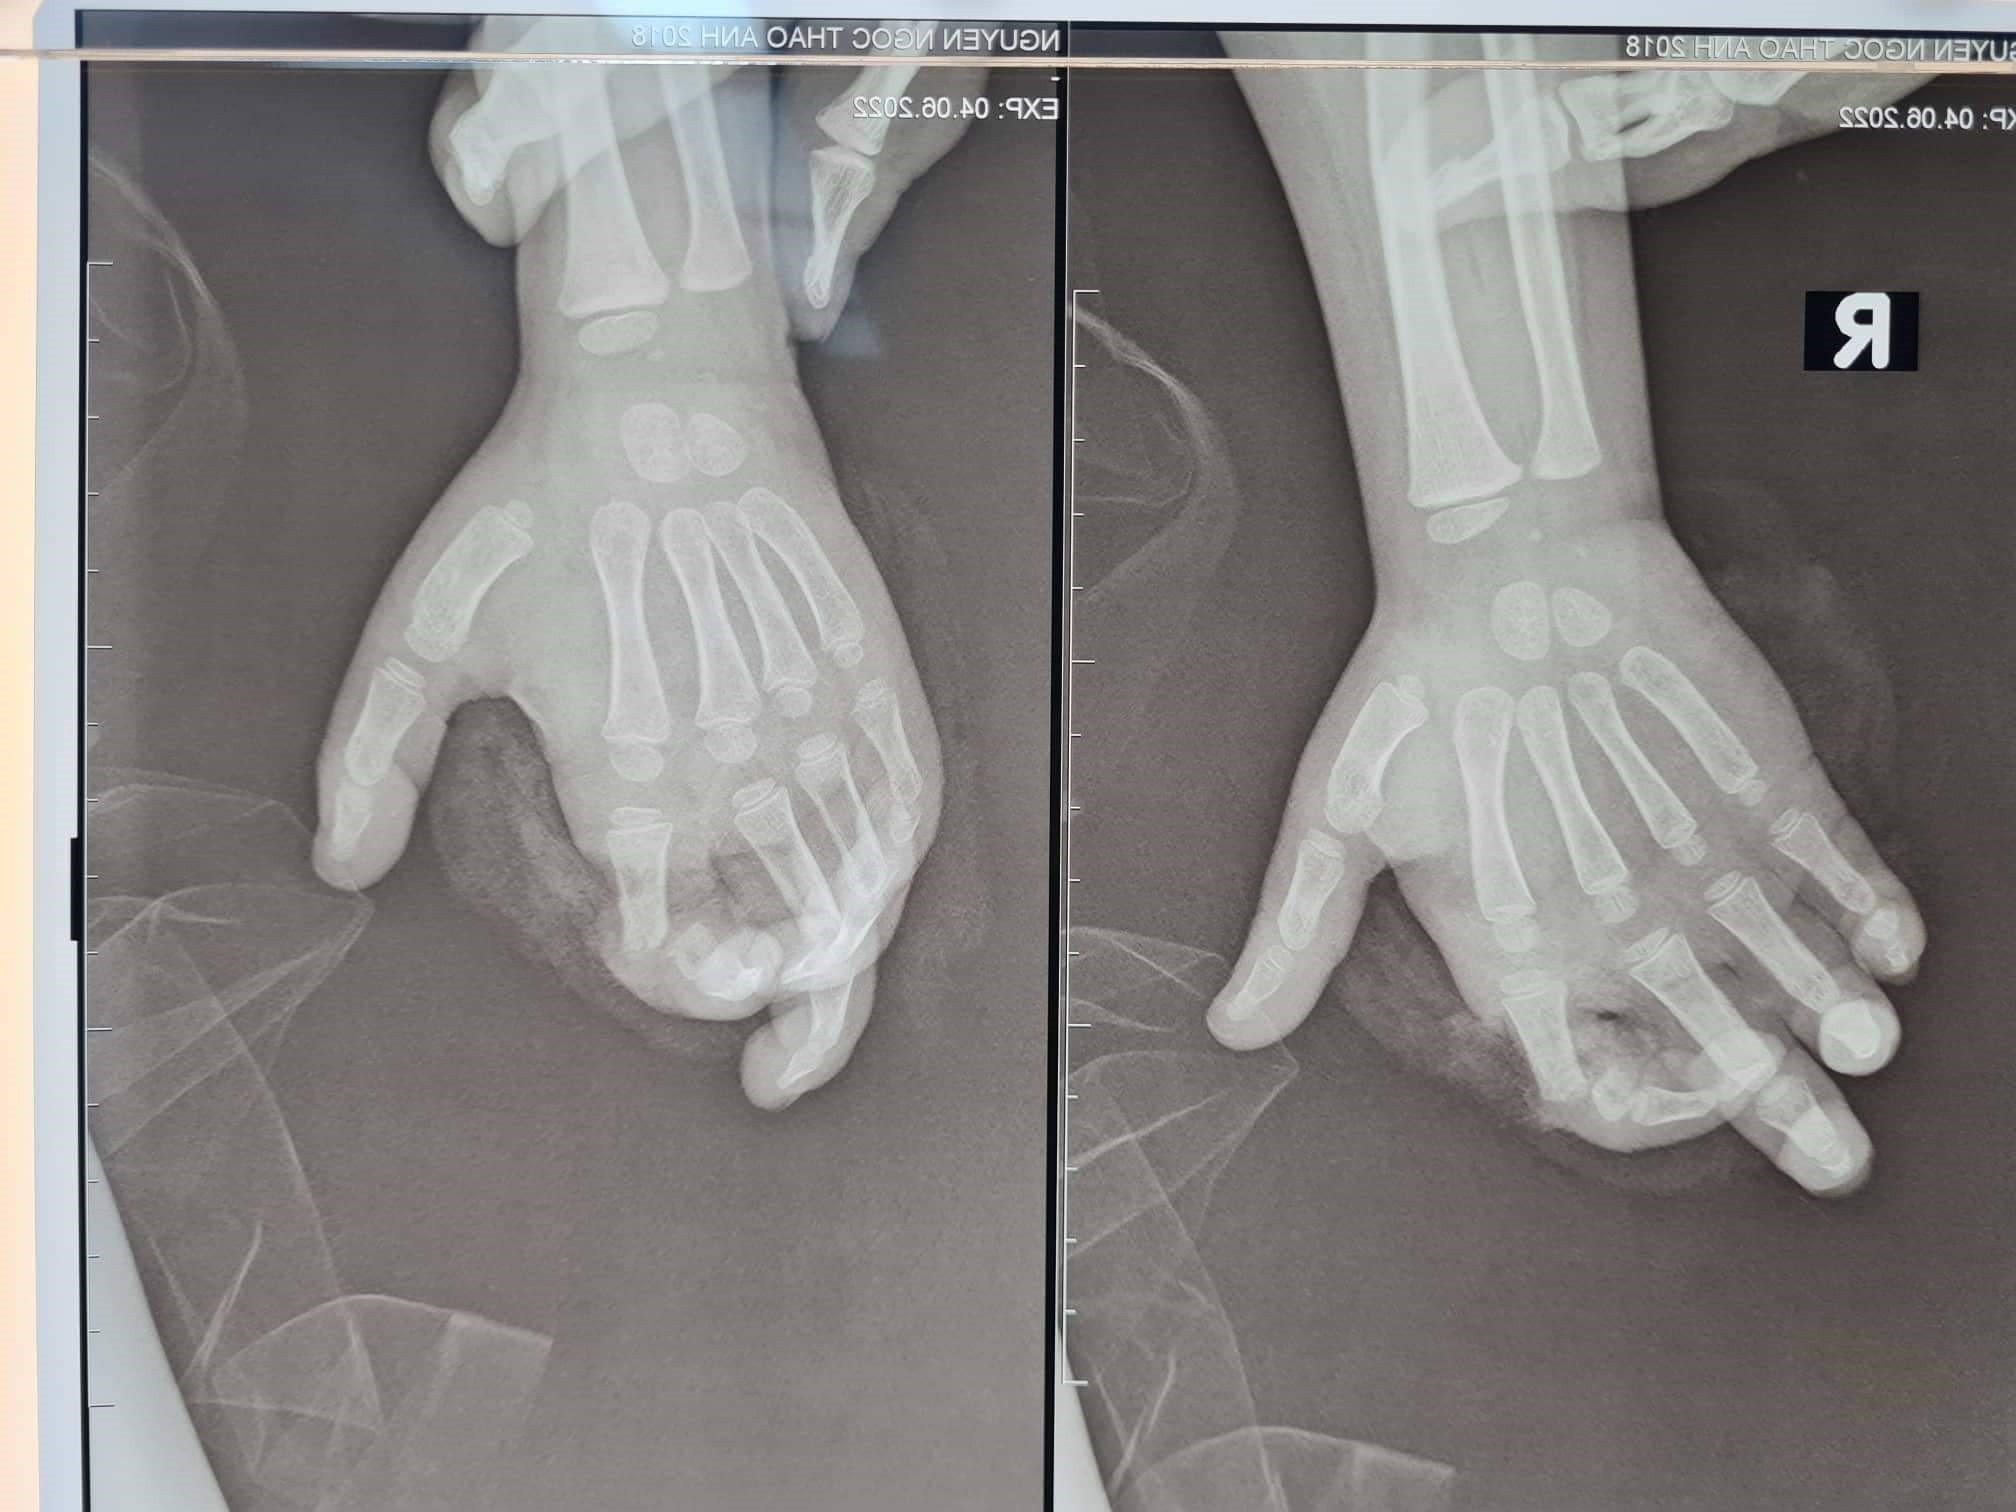

TS.BS Nguyễn Quang Vịnh, khoa Phẫu thuật Chi trên và Vi phẫu thuật, cho biết, bệnh nhi vào viện do bị máy nghiền hoa quả nghiền vào bàn tay phải. Sau tai nạn, T.A bị đứt gần rời ngón 2 tay phải (ngón 2 tay phải chỉ còn dính lại gân gấp), phần ngón đứt gần rời trắng bệch do không được cấp máu.

Các bác sĩ phải kết lại xương, khâu nối gân duỗi, nối thần kinh và đặc biệt là phải nối lại mạch máu (gồm các động mạch và tĩnh mạch) để cung cấp lại máu cho ngón tay. Do kích thước mạch máu ở trẻ em rất nhỏ, tổn thương lại do máy nghiền, bầm dập nhiều nên việc nối lại ngón tay cho bệnh nhi rất khó khăn.